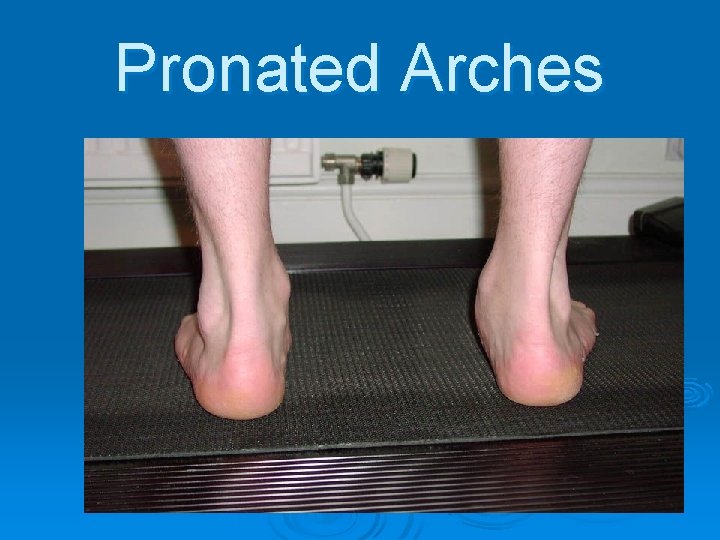

Pronated Arches (Flat Feet)

Pronated Arches

Pronated Arches

Pronated Arches